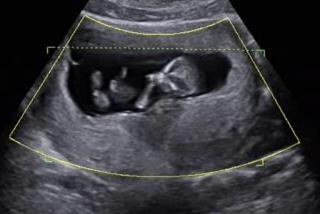

Statystyki pokazują, że istniejący w irlandzkim prawie okres oczekiwania przed aborcją przynosi dobre efekty. Około 1500 Irlandek w 2020 roku zdecydowało się nie poddawać aborcji po wstępnej konsultacji.

Druzgocące dane z Irlandii. Ponad dwa razy więcej aborcji po zmianie prawa

Według danych opublikowanych na początku lipca przez irlandzkie Ministerstwo Zdrowia w Irlandii od początku 2019 roku, czyli od czasu liberalizacji prawa aborcyjnego, zabitych zostało 13 709 nienarodzonych dzieci. W 2020 roku dokonano ponad dwa razy więcej aborcji niż w roku 2018.

Irlandia: 6666 ofiar aborcji w pierwszym roku po jej legalizacji

6666 nienarodzonych dzieci zabito w wyniku aborcji w zeszłym roku w Irlandii, w czasie pierwszego roku obowiązywania nowej ustawy pozwalającej na praktycznie nieograniczone przerywanie ciąży.

Biskupi w Irlandii wzywają do przeciwstawienia się nowemu prawu, które pozwala na aborcję na życzenie do 12 tygodnia ciąży. Weszło ono w życie 1 stycznia. Musimy nadal wzywać i pracować pilnie nad jego ograniczeniem i uchyleniem – mówił przewodniczący tamtejszego episkopatu.

Od 1 stycznia w Irlandii prawo pozwala na aborcję bez uzasadnienia

Od 1 stycznia 2019 w Irlandii weszła w życie liberalizacja przepisów aborcyjnych. Obecnie do 12 tygodnia ciąży można dokonać aborcji bez konieczności jej uzasadnienia